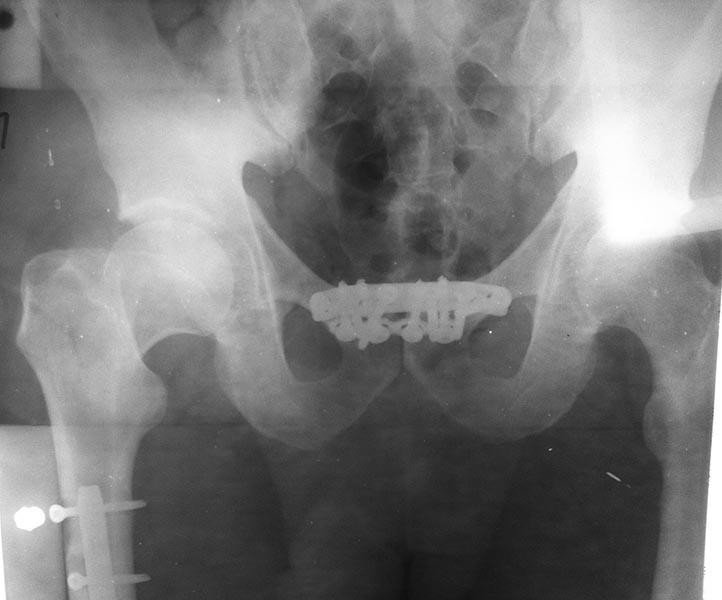

правого бедра. 13.02.2013г. - выполнены металлостеосинтез перелома правой

большеберцовой кости пластиной, лонного симфиза двумя пластинами. Пациент

тактике лечения? Снимки: 1. При поступлении. 2. Послеоперационный. 3. от

05.03.2013г.

Имя     : IMG_3038[1].JPG

Тип     : image/jpeg

Размер  : 50356 байтов

Описание: отсутствует

Url     : http://weborto.net:8080/pipermail/ortho/attachments/20130306/d918acc1/attachment-0003.jpeg